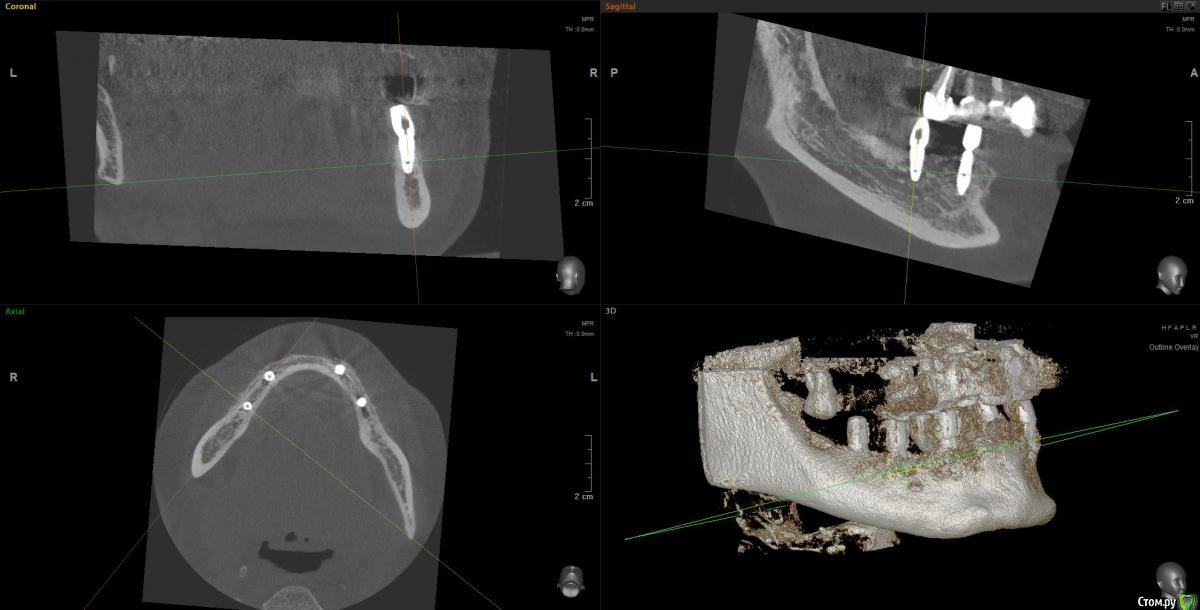

Kostoprav Опубликовано 14 июня, 2019 Поделиться Опубликовано 14 июня, 2019 Ксено+ауто +i prf, поверх титановых мембран перикард. кт через 5 мес.при и создании прикрепленки использовалась свиная дерма отечественного производителя 4 Ссылка на комментарий

vgraev Опубликовано 20 июня, 2019 Поделиться Опубликовано 20 июня, 2019 спасибо за клинический случай! скажите,пожалуйста, это сетки,фиксированные заглушками, или смарт билдеры со спейсерами? Ссылка на комментарий

Kostoprav Опубликовано 28 июня, 2019 Автор Поделиться Опубликовано 28 июня, 2019 спасибо за клинический случай! скажите,пожалуйста, это сетки,фиксированные заглушками, или смарт билдеры со спейсерами?сетки фиксировал спейсерами Ссылка на комментарий